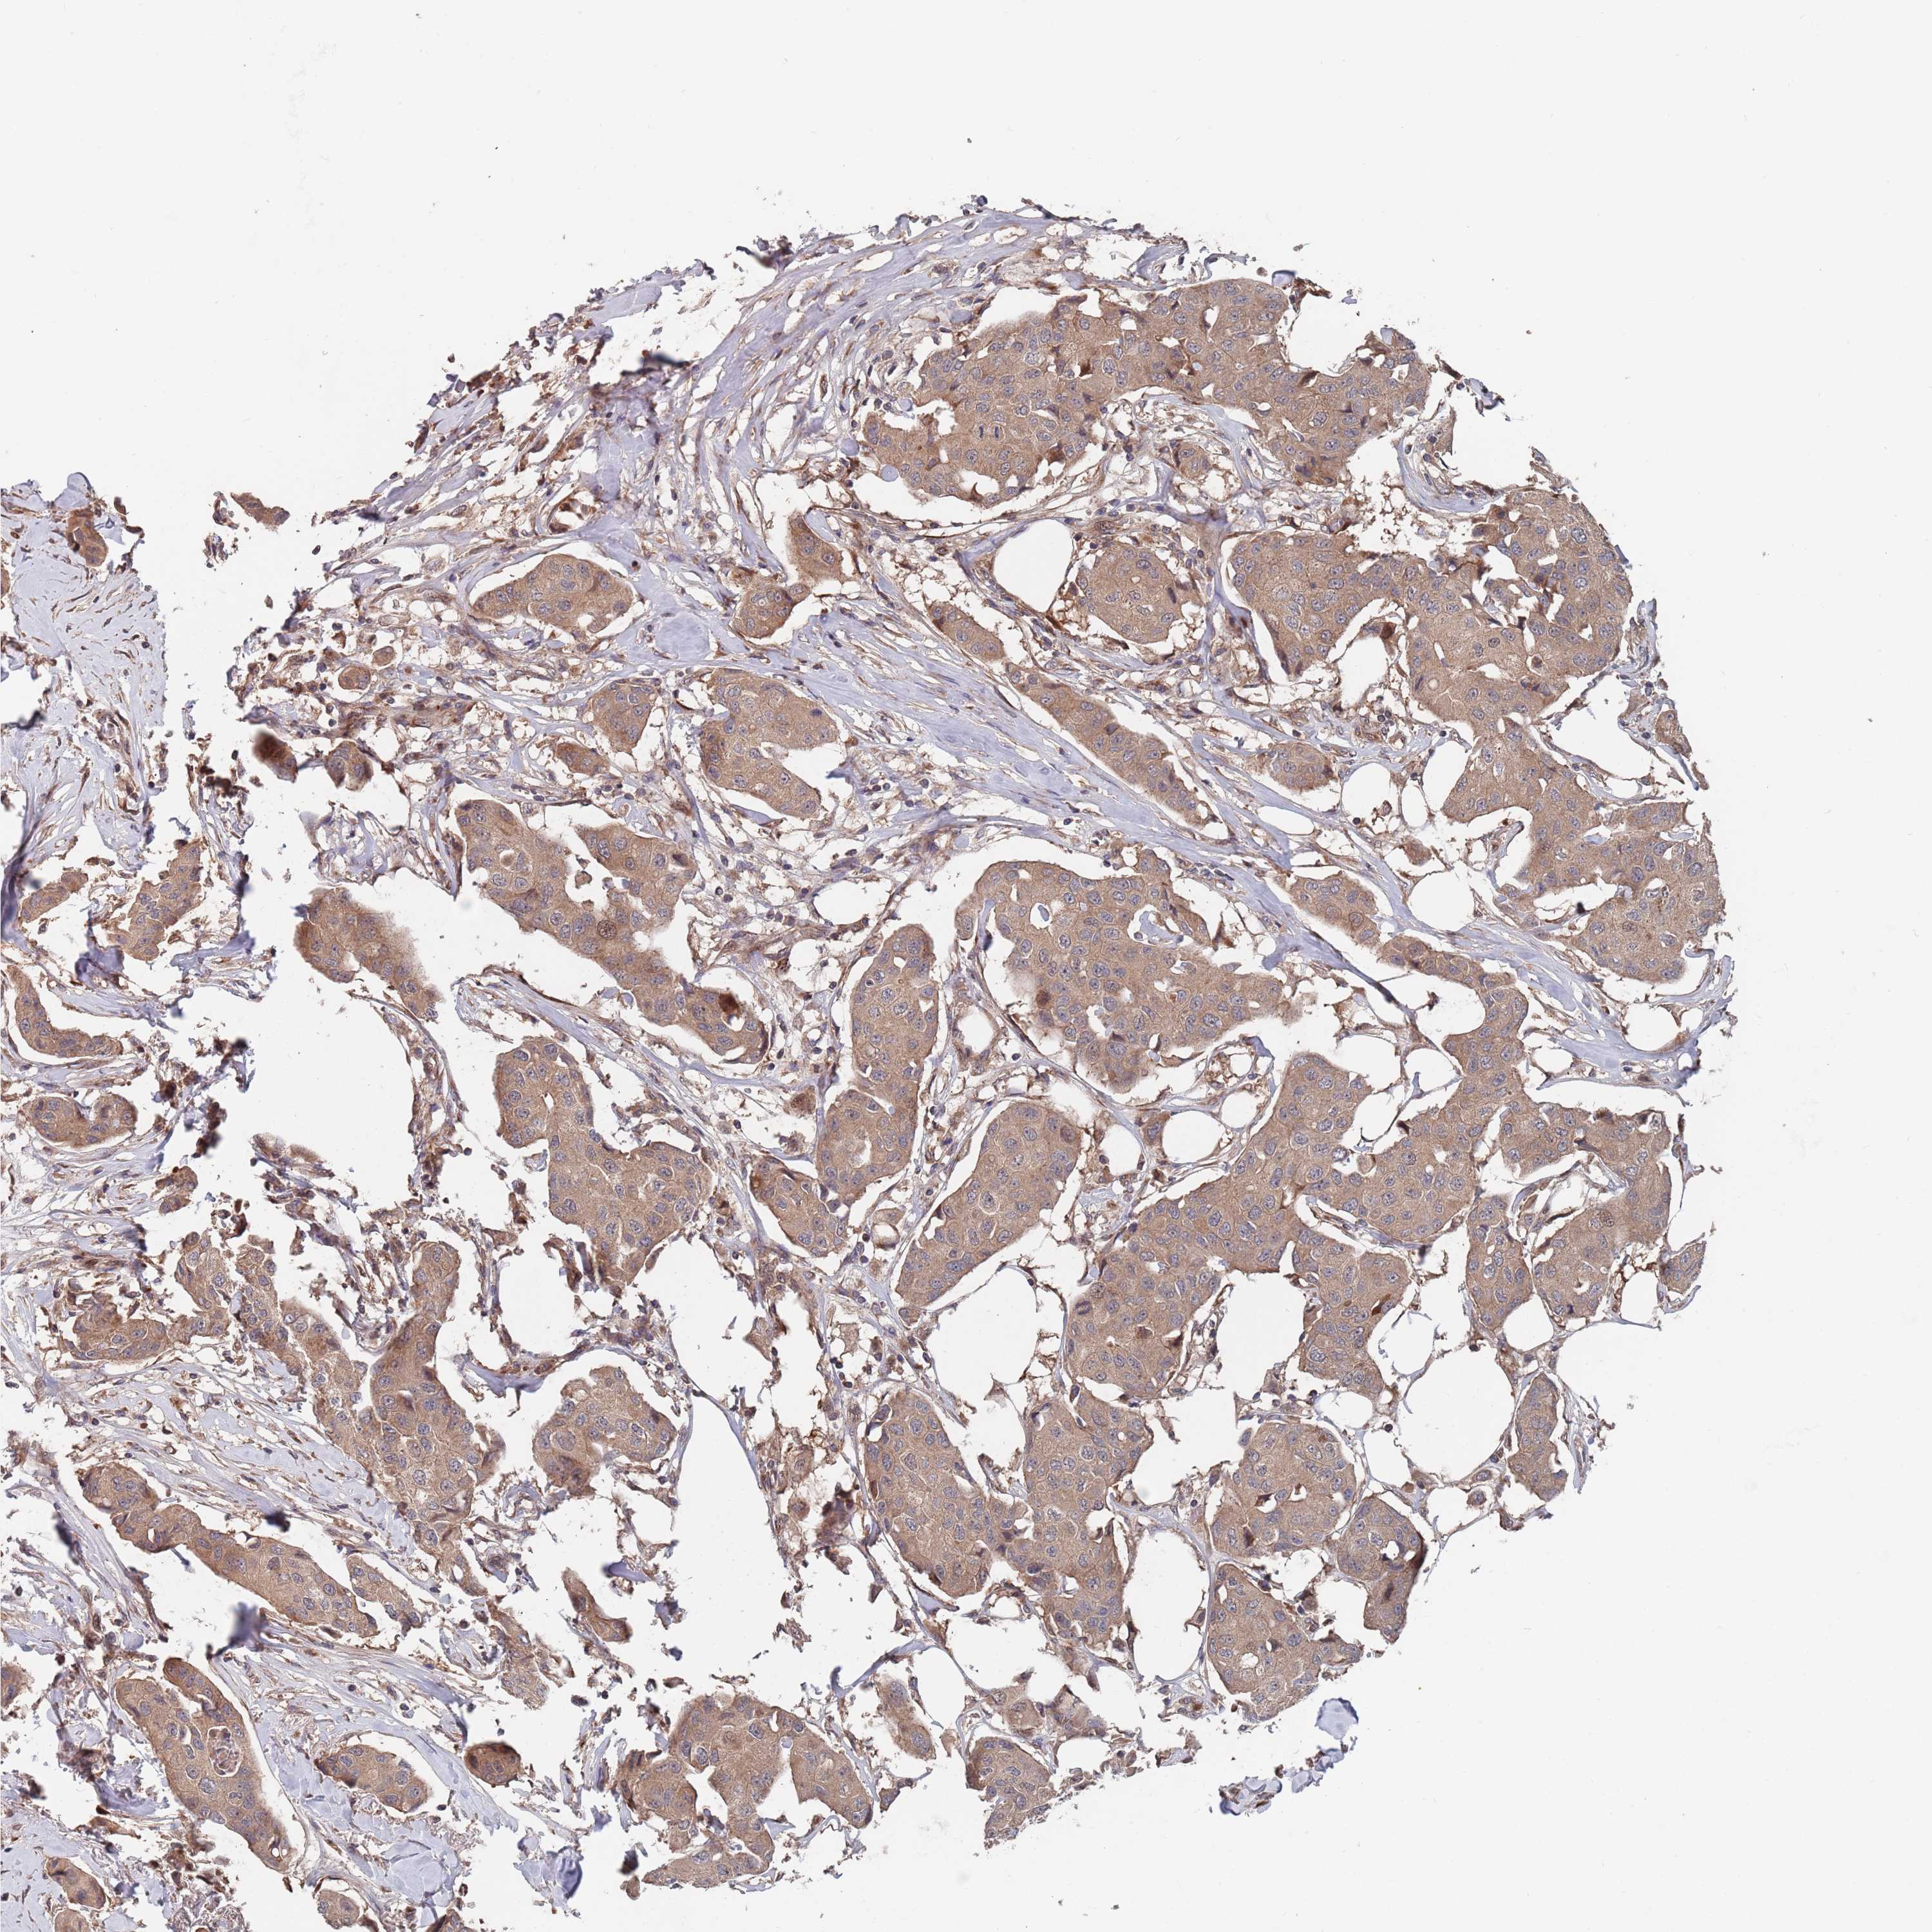

BRCA TCGA BRCA VALIDATION PROTEIN EXPRESSION